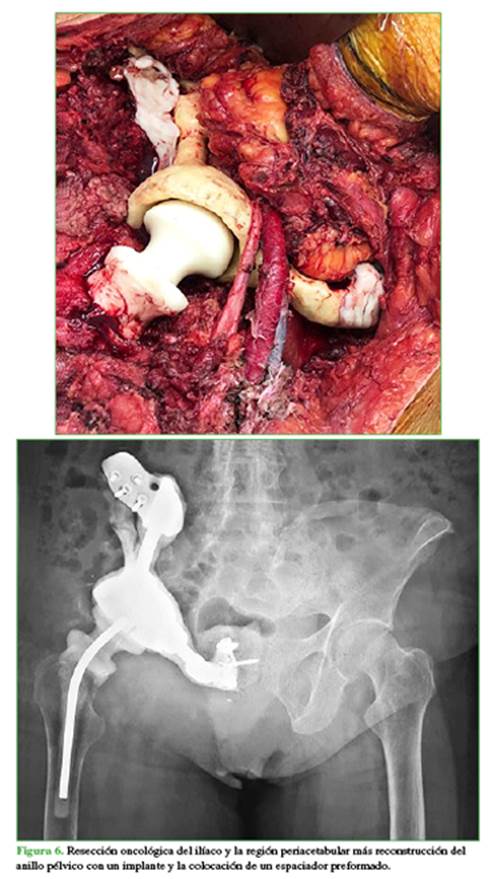

Se realizó la resección oncológica del ilíaco y la región periacetabular, y se envió la pieza para estudio anatomopatológico (Figura 5); luego se procedió a la reconstrucción del anillo pélvico con un implante y la colocación de un espaciador preformado (Figura 6). El estudio histopatológico posterior indicó márgenes libres.